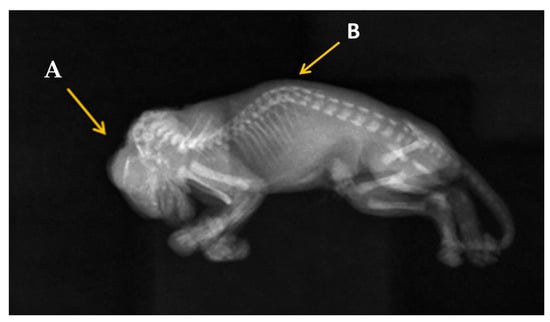

2.4. Radiography Investigation